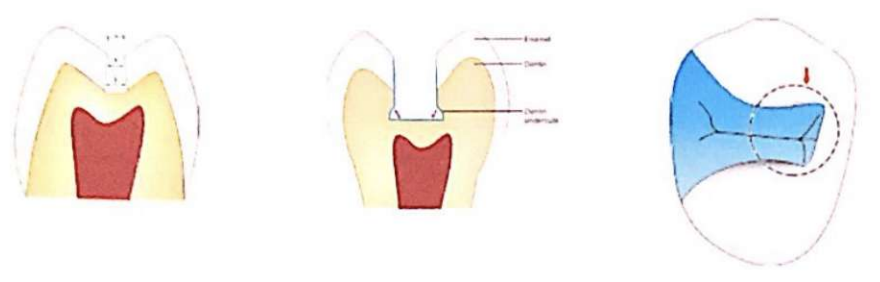

- Cavité occlusale : Préparée avec un plancher pulpaire plat, à 0,5 mm de la jonction émail-dentine, avec des parois opposées parallèles. La fraise à fissure plate est positionnée perpendiculairement au plancher pulpaire et étendue vers la crête marginale proximale.

- Largeur de l’isthme : Réduite au minimum, ne dépassant pas 1/4 de la distance inter-cuspidienne ou 1,0 à 1,5 mm.

- Charges masticatoires : Une largeur vestibulo-linguale minimale est maintenue pour les fortes charges masticatoires.

- Convergence occlusale : Les parois dentinaires convergent de 2 à 5 % vers la surface.

- Contre-dépouille légère : Réalisée dans la dentine près de la paroi pulpaire.

- Préparation en forme de boîte : Offre une structure robuste.

- Plancher pulpaire et gingival plat : Résiste aux forces occlusales sans déplacement.

- Épaisseur adéquate du matériau : Adaptée à la résistance à la compression et à la traction (ex. : 1,5 mm minimum pour l’amalgame à haute teneur en cuivre).